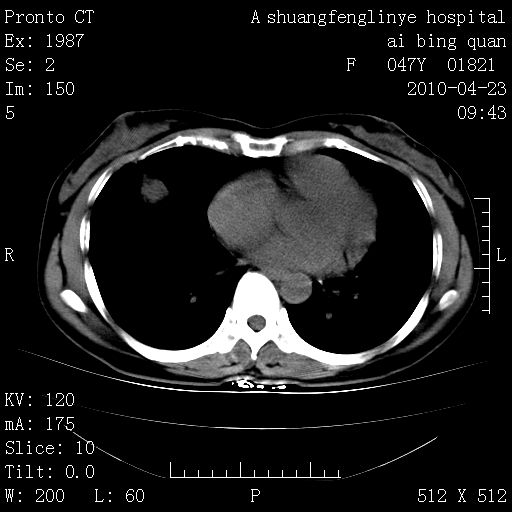

标题: CT25944:胸痛、气短、前几日高烧!肺Ca?请会诊! [打印本页]

标题: CT25944:胸痛、气短、前几日高烧!肺Ca?请会诊!

kaolv 周围型肺癌并同肺转移

双肺多发结节,考虑转移瘤,肺癌肺转移不除外

周围型肺癌并肺转移

双肺多发结节,部分密度较高,最大结节边缘光滑。临床有“胸痛、气短、前几日高烧”病史。首选考虑:右肺感染性病变!建议积极消炎后复查!